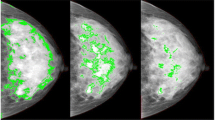

Study 1: screen-detected cancers

In study 1 after full adjustment, the strongest predictor of breast cancer risk was visually assessed density (Table 2, Fig. 1), with an odds ratio (OR) of 4.37 (95% CI 2.72–7.03) in the highest quintile of density compared with the lowest. When quantized in Boyd categories (Table 3), the adjusted OR of those with greater than 50% density was 6.73 (95% CI 3.64–12.45) compared to those with density 10% or lower. Volpara percent density provided the next strongest association with cancer, with an OR for the highest quintile of 2.42 (95% CI 1.56–3.78) (Table 2, Fig. 1). When quantized in Volpara Density Grades (VDG 5th edition), the OR of VDG4 was 4.39 (95% CI 2.28–8.48) compared with VDG1 (Table 3). Both visually assessed density and Volpara percent density showed a significant and clear trend with increasing density (χ2 trend 35.6, p < 0.001 and 11.2, p < 0.001, respectively). Percent density measured by Densitas and Cumulus was also statistically significant (Table 2, Fig. 1), with ORs of 2.17 (95% CI 1.41–3.33) and 2.12 (95% CI 1.30–3.45), respectively in the highest quintile of percent density compared with the lowest, and for Quantra there was no significant association (OR = 1.02, 95% CI 0.67–1.54). The relationship with dense volume is shown in Table 2; generally associations tended to be slightly lower than those for percent density. In the subset of women with all density measures VAS was a significantly better predictor of breast cancer risk than all other methods (Table 2, Additional file 1: Table S2). The matched concordance index for VAS was 0.651 (95% CI 0.611–0.691) demonstrating better discrimination between cases and controls than all other methods (Table 4).